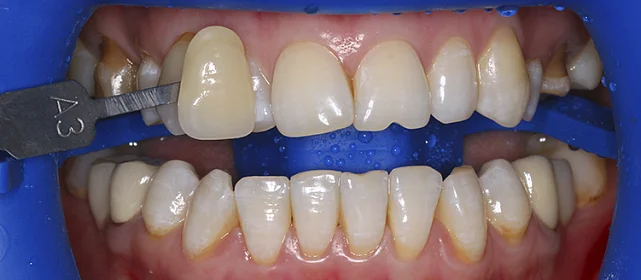

Проблема: В клинику обратился мужчина с жалобами на неправильное положение зубов и смыкание — ряды сходились некорректно, зубы стояли со смещением. При этом было важно, чтобы лечение оставалось незаметным для окружающих, поэтому вариант с брекетами не рассматривался.

Решение: Поставили элайнеры Invisalign на обе челюсти. Лечение заняло 4 года — случай потребовал нескольких этапов коррекции, каждый из которых последовательно приближал зубы к нужному положению. Капы менялись каждые 1–2 недели, контрольные визиты — для отслеживания прогресса и выдачи новых наборов. Зубы встали на место, смыкание пришло в норму. Зафиксировали ретейнеры на обе челюсти, пациент направлен к ортопеду для завершающего этапа.

Случай потребовал нескольких последовательных этапов коррекции. Invisalign позволяет дозаказывать капы в рамках лечения, и здесь это понадобилось — каждый следующий этап доводил положение зубов точнее. Результат достигнут, прикус стабилен, ретейнеры на месте. Пациента направила к ортопеду.